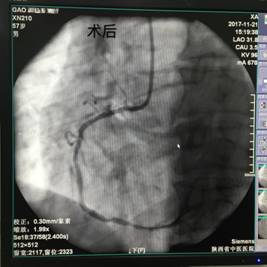

11月21日上午11:30分许,患者高某在家属陪同下来我院急诊科就诊,当班医生车玲艳主治医师接诊后详询病史,患者自述突发胸痛、胸闷,逐转至抢救室,给予心电监护、吸氧,建立静脉通路,床旁查体,急查心电图及相关实验室检查,心电图结果提示急性下壁心肌梗塞,上报科主任,立即抢救,急请心病科会诊,当班医生一边说一边展开抢救。屈小元主任医师立即组织抢救,在予扩管、抗凝、抗血小板等药物治疗后,患者胸痛症状稍有缓解。心内科张笑峥副主任医师会诊后建议立即行急诊介入手术,家属救治态度积极,患者被紧急转至导管室进行PCI,术中患者出现再灌注后心律失常,张广平副主任医师等人积极抢救治疗,成功开通闭塞血管,完成右冠脉内支架置入,术后患者情况稳定,转入心病科病房进行监测及后续治疗。

手术前、后对比

手术进行中